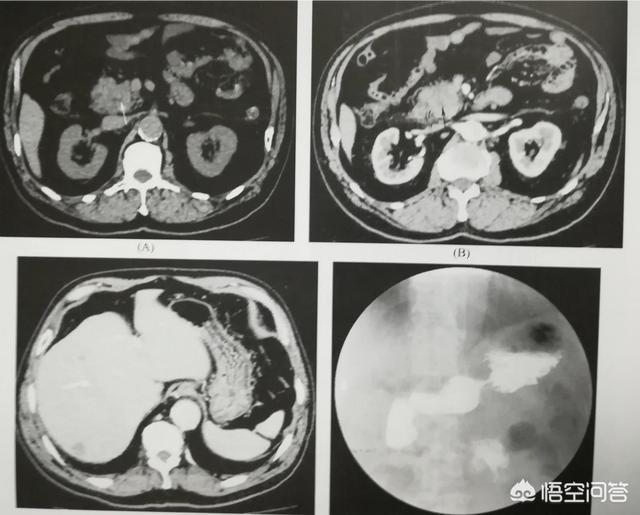

(如图为胰腺钩突部癌。63岁。患者两年前突发血糖升高。一直以为正常糖尿病。去年底被诊断为胰腺癌)

因此。对于50以上的人群。若新近发现糖尿病。应引起大家足够重视。有可能是胰腺癌的异常症状。属于患胰腺癌的高危人群。